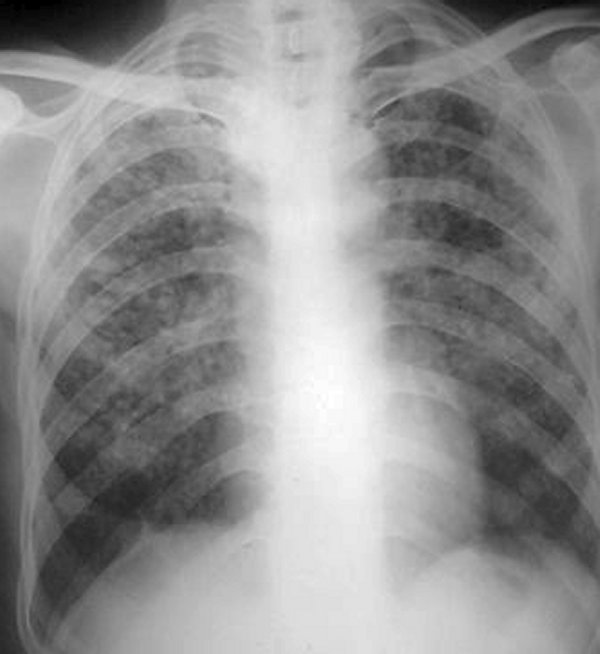

Silicoză gradul II/III